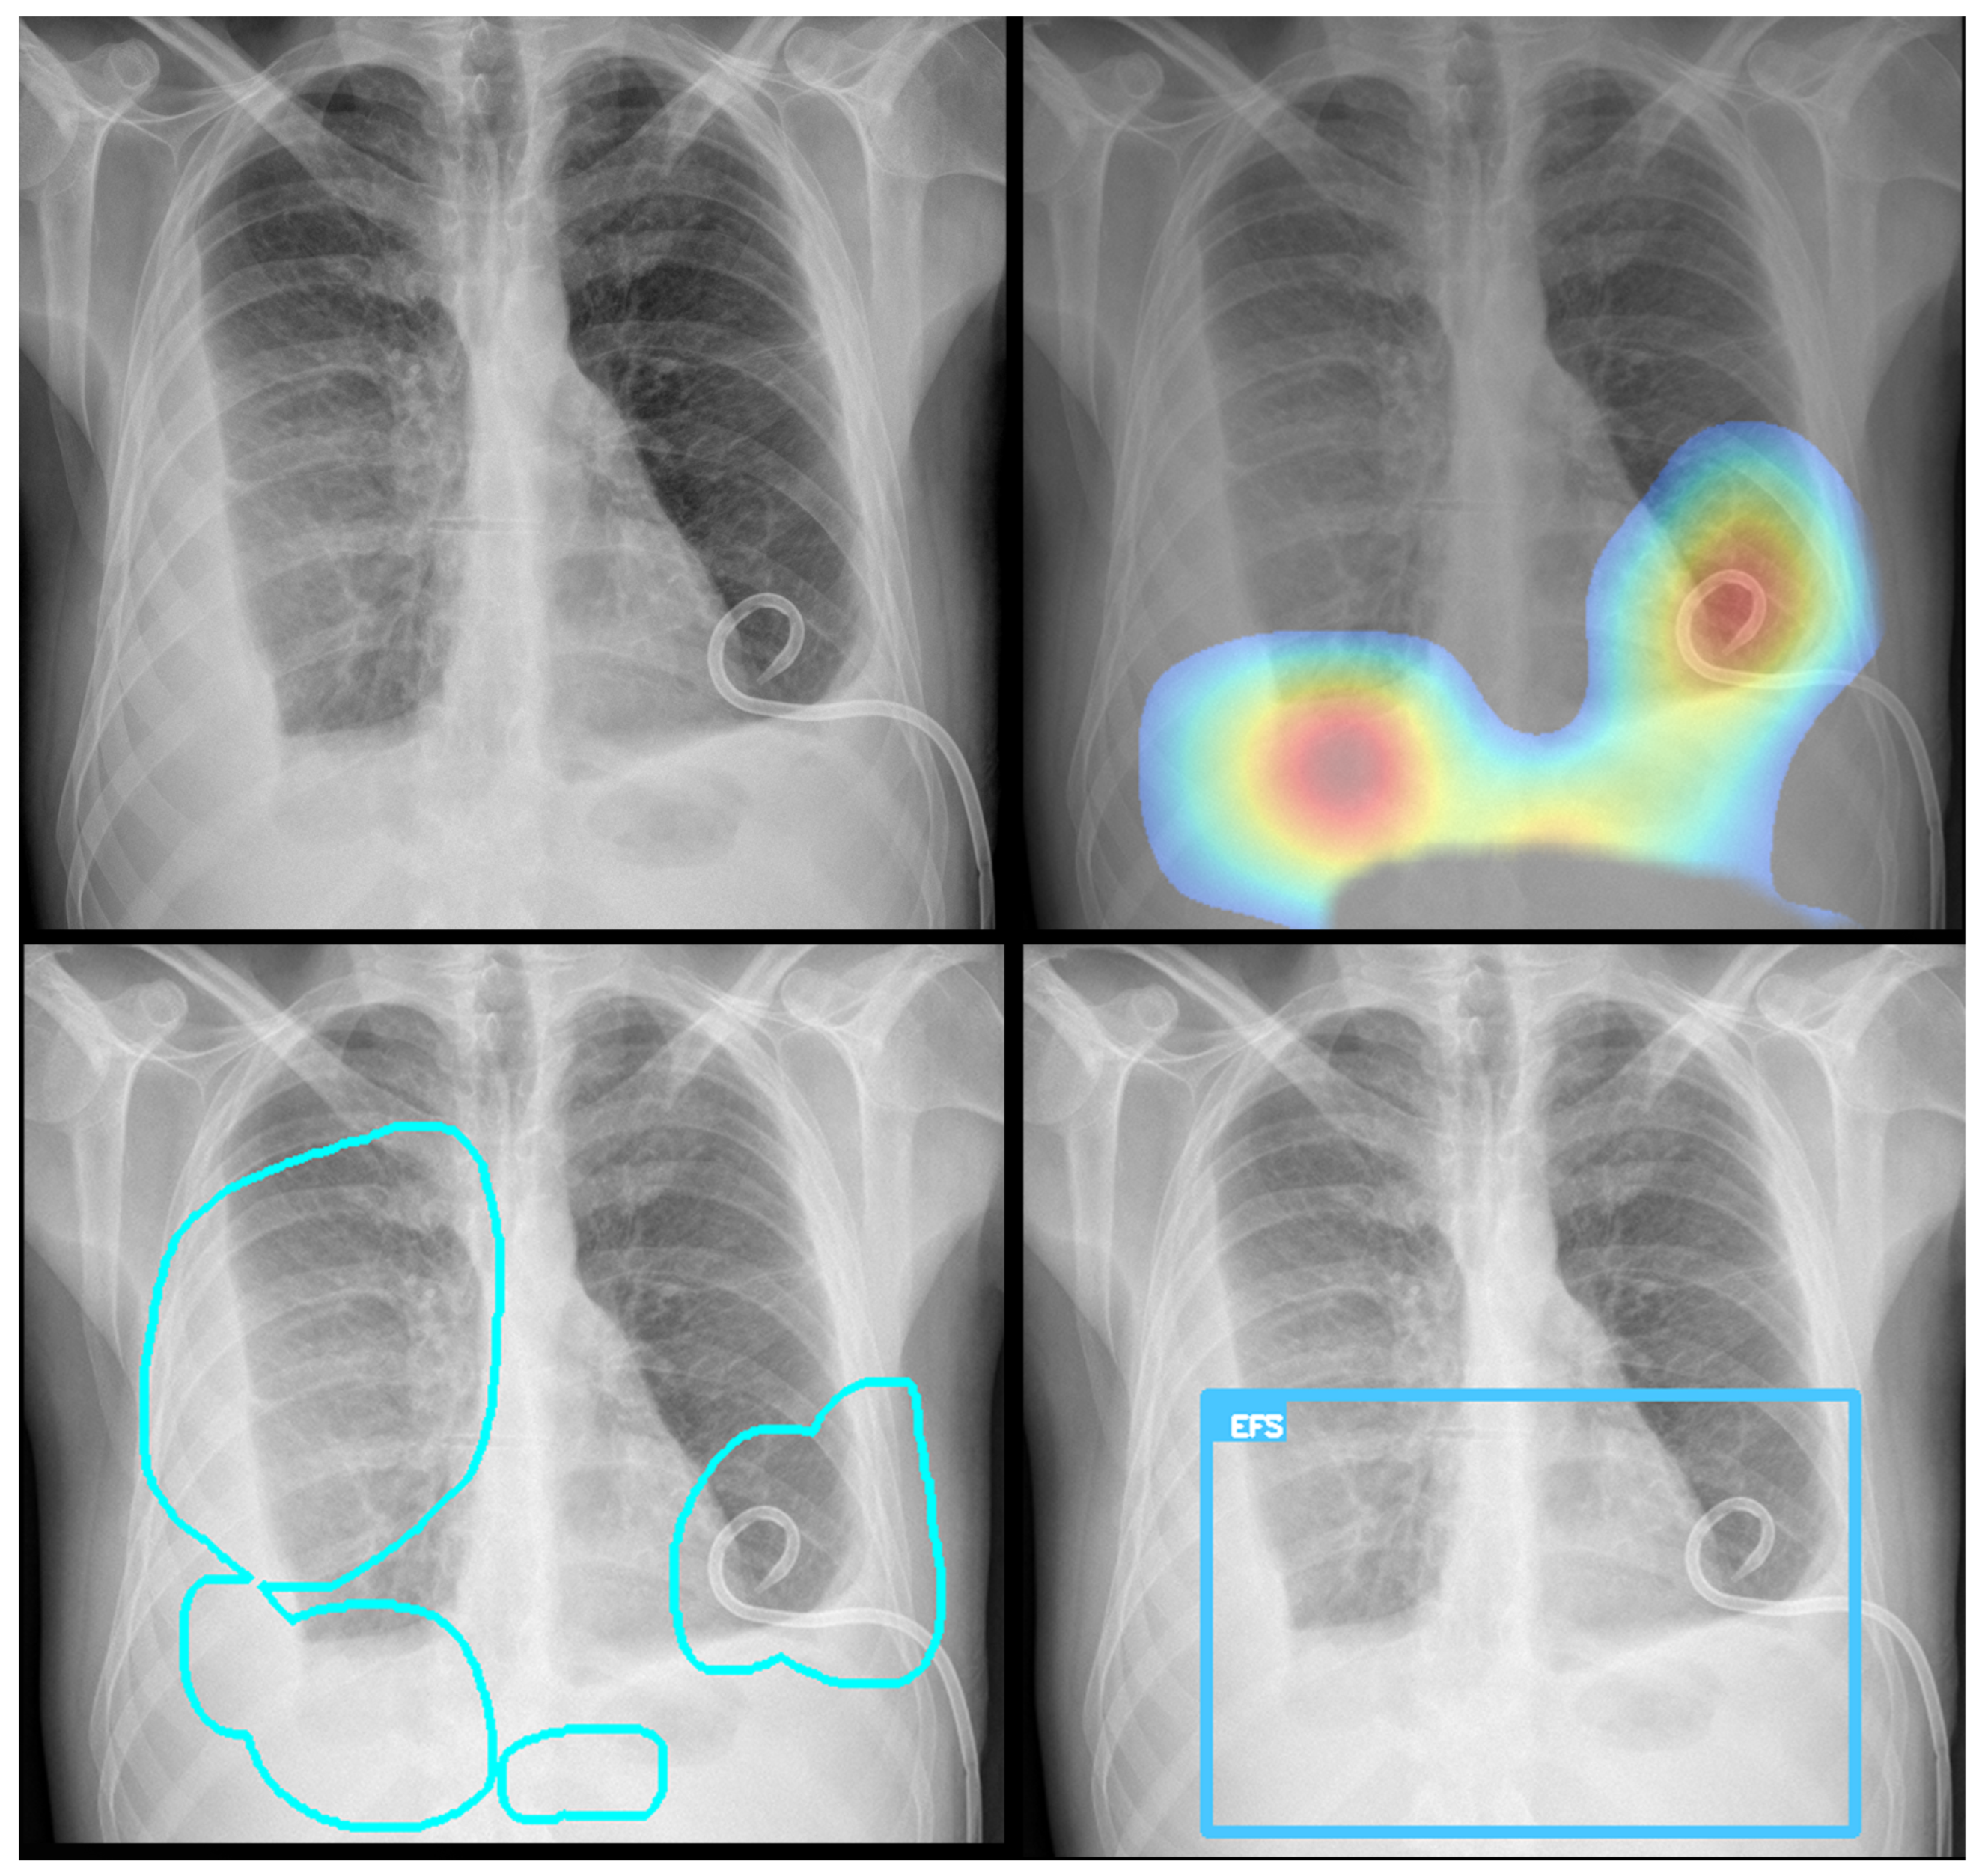

Before training, radiologists reviewed and verified the images, applying annotations using a proprietary software application (Figure 1). The dataset exhibited a significant class imbalance, reflecting the real-world prevalence of the pathology. For training binary classifiers, studies with definitive labels (1.0 for present, 0.0 for absent) were used. In contrast, studies with missing labels for a specific finding were excluded from the loss calculation for that task. Table 2 shows the distribution for a selection of key labels. The list of pathologies was selected based on the availability of labeled data, balanced with clinical importance for the ED. The ‘normal’ and ‘abnormal’ pools included cases with pathologies beyond the specifically targeted list; these were categorized under the general “yesfinding” class.

Figure 1. All labeled images were proofed by a radiologist who manually drew a region of interest around the pathology and assigned a finding, as shown here for an alveolar opacity circled by the dashed line.

Figure 3. Example of Grad-CAM visualizations localizing detected findings. The figure shows the original image (top left) alongside three types of explanatory outputs generated by the algorithm: a heatmap (top right), a contour outline (bottom left), and a bounding box (bottom right). All visualizations are derived from the same process, showcasing different output options.